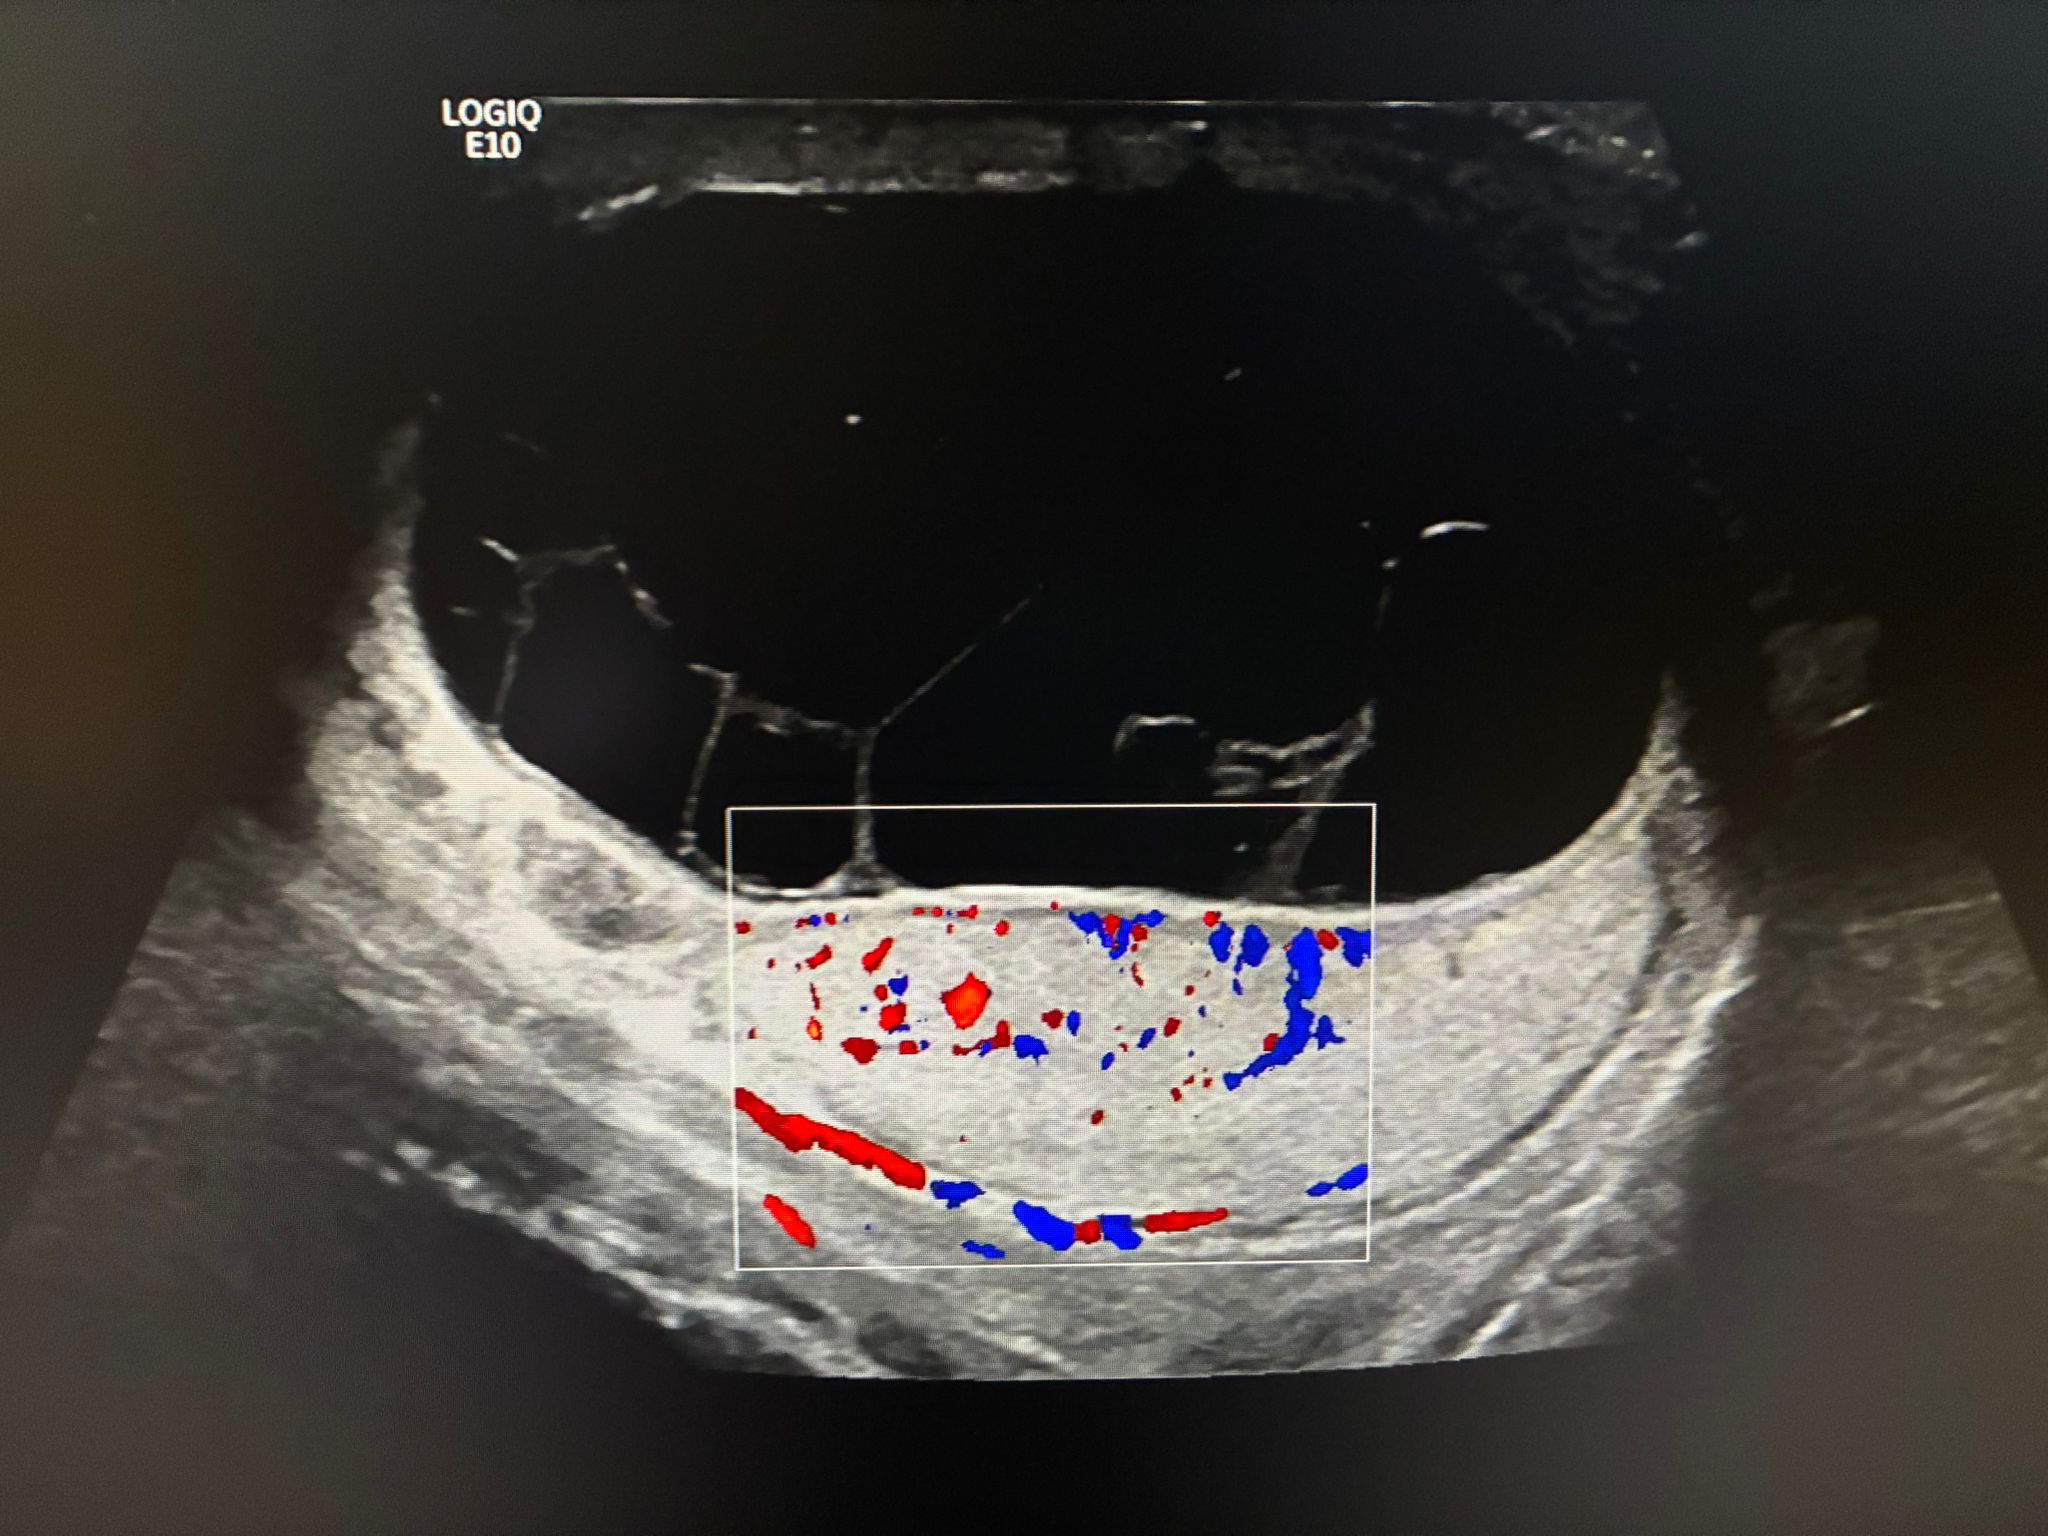

Ecografía reglada: Hidrocele multitabicado en bolsa escrotal derecha en probable relación con piocele en el contexto clínico. Teste derecho comprimido con discreto aumento de su ecogenicidad. Engrosamiento de cubiertas escrotales derechas. Se observa hiperemia a nivel testicular y epididimario derecho, hallazgos que pueden estar en relación con orquiepididimitis. Teste izquierdo de tamaño y morfología normal.